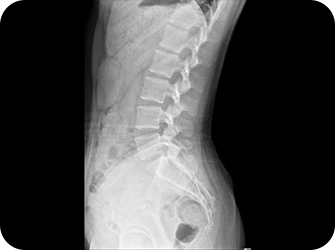

허리(요추)

허리의 3대 질환

허리 디스크, 협착증, 척추전방전위증

요통의 가해자로 지목되는 허리디스크

실제로는 피해자입니다.

허리 통증의 주요 가해자 허리디스크, 협착증, 척추전방전위증, 요추염좌, 디스크내장증, 압박골절, 척추분리증 등 이름은 다양하지만 따지고 보면 틀어진 자세로 인해

골반과 24개의 척추뼈가 중력을 버티는 과정에서 척추 하부에 있는

요추 3,4,5번에 압력이 집중된 결과일 뿐이고 그 결과물에 여러 가지 병명을 만들어 붙여 나온 질환일 뿐입니다.

따라서 실제 허리통증의 가해자는 허리디스크에 압력을 증가시킨 골반 틀어짐이나 다리길이 차이, 거북목, 틀어진 어깨, 측만증 등의 자세불균형입니다.

Vertebrae Lumbales